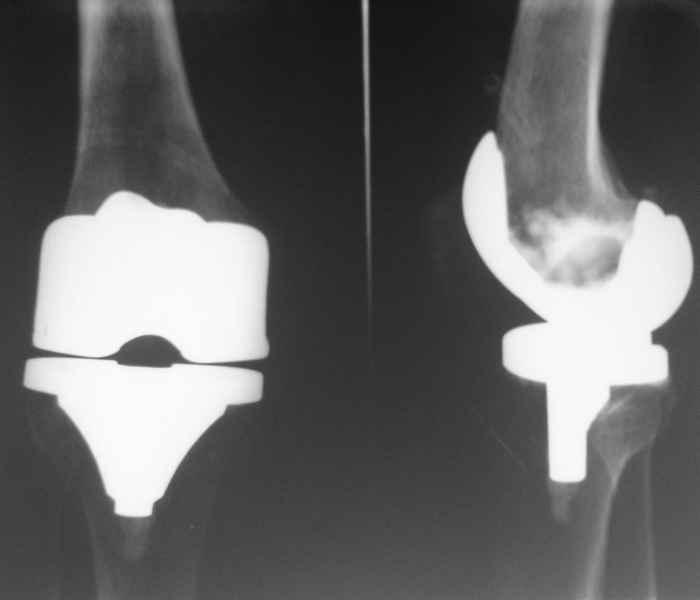

Уважаемые коллеги, Прошу совета. В феврале 2007 года пациентке выполнено эндопротезирование коленного сустава.

13/02/07 |  25/07/07 |  дек. 07 |  25/06/08 |  14/01/09 | Через 1 месяц после операции объем движений 90 градусов, через 2 месяца 60, через 3 - 40, через 5 - качательные движения.

В июле 2007 года выполнена ревизия - полости сустава нет. Капсула сустава имеет толщину от 1 до 1.5 см, собственная связка надколенника имеет толщину до 3 см. Сустав заполнен фиброзно-рубцовой тканью. Компоненты стабильны.

Есть вопросы к установке протеза. Скорее всего тибиальное плато было не конца резецировано и в задненаружных отделах осталась ступенька. Это привело к тому, что тибиальный компонент завалился на варус.

Ты мне говорил об этом случае, а теперь я увидел снимки. Для исключения или подтверждения гнойного процесса надо взять обязательно посев. По-моему и бедро шатается. Ревизовать при ислючении гнойно-септических осложнений надо полностью либо CCK комплектом или связанным.

По представленным снимкам (patella infera) и по клиническому описанию у Вашего больного типичный Артрофиброз (Knee Arthrofibrosis) обычное после замены сустава осложнение, характеризуется ограничением движения в суставе за счет образования рубцовой ткани. Такое осложнение встречается и после травм коленного сустава или после восстановительных работ на передней крестообразной связке.